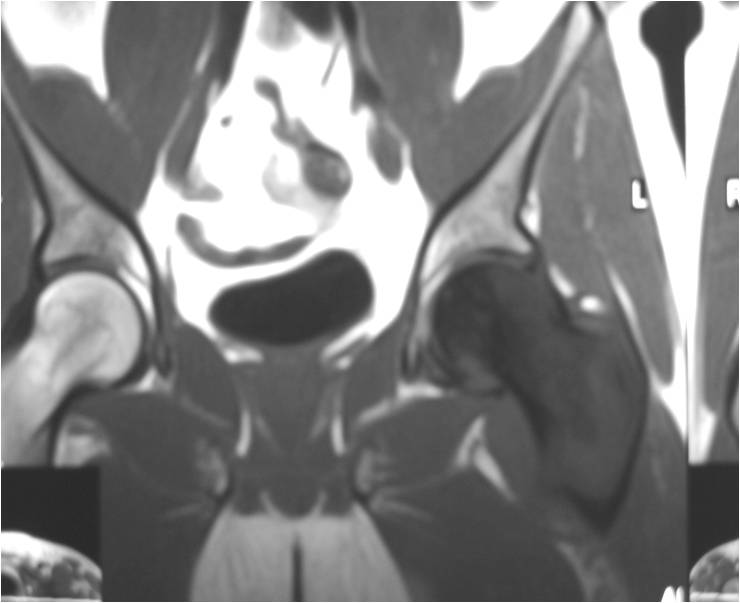

TI Weighted MRI

- Soft tissue mass— by CT (80%); by MRI (100%)

- Diffuse infiltrative growth pattern with soft tissue extension

- Intraosseous component

- Mixture of bone spicules and marrow fat as lesion permeates through the medullary canal and has an indistinct margin